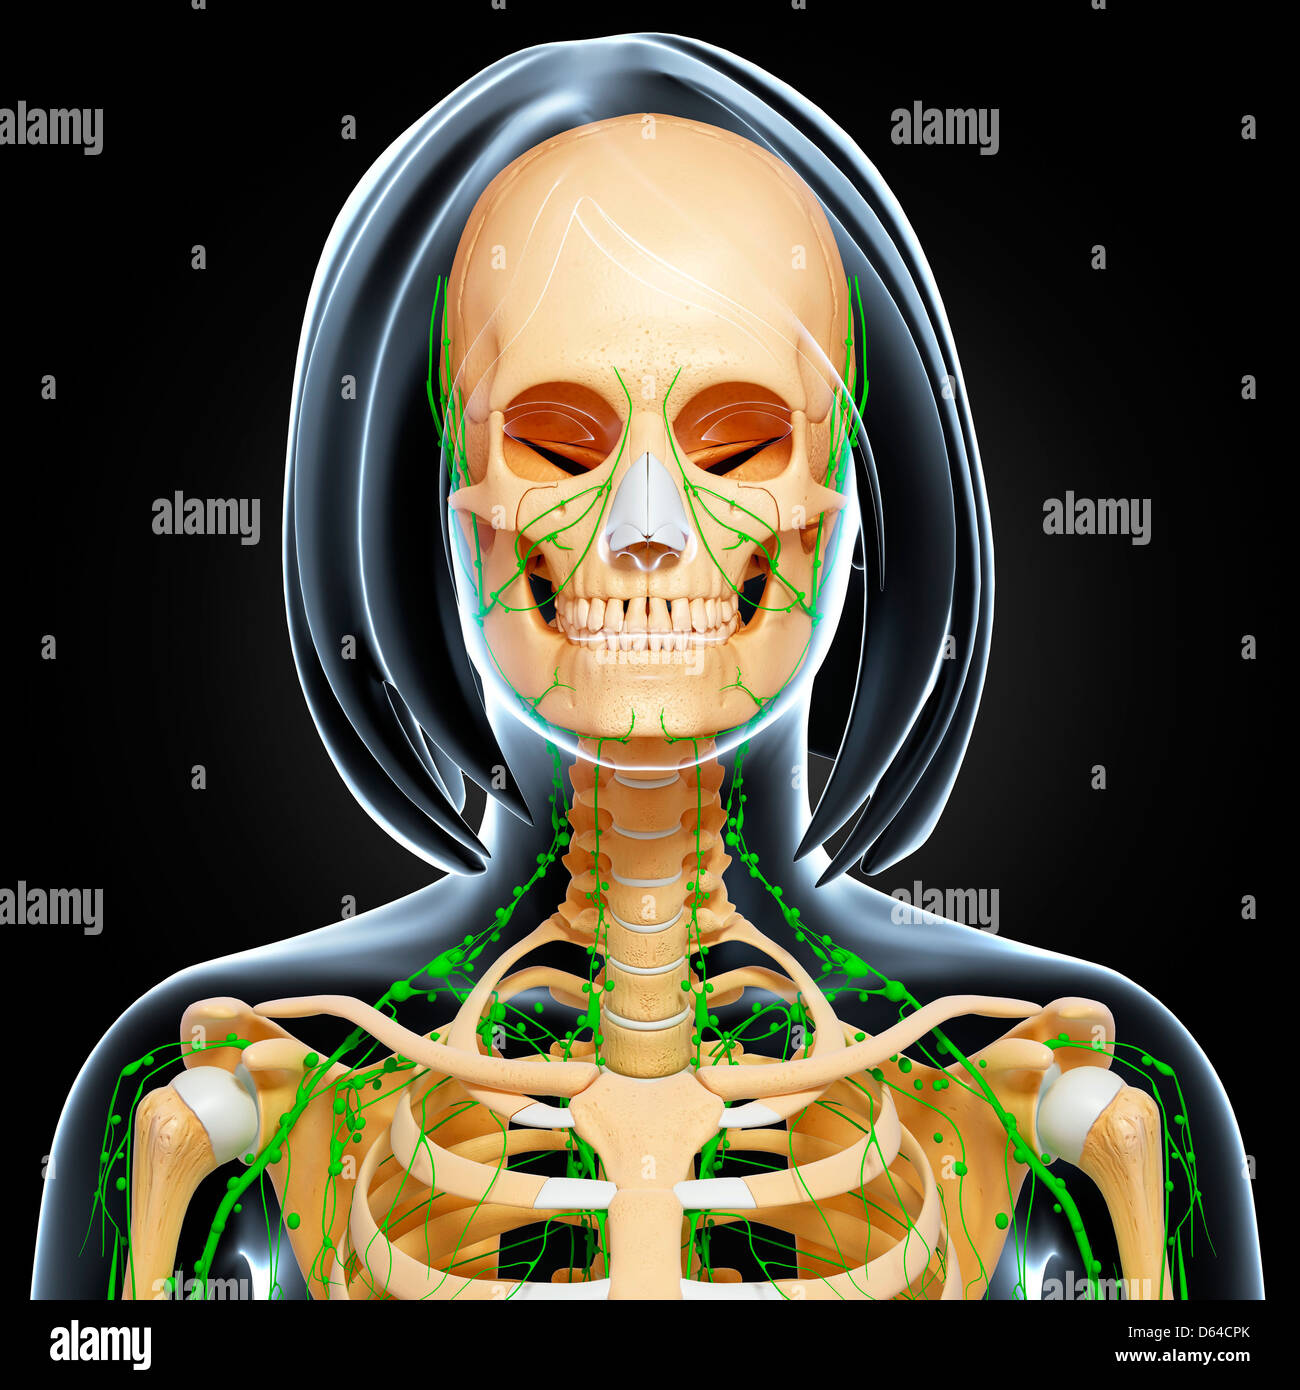

Female Anatomy Photograph By Pixologicstudio/science Photo Library

fineartamerica.comFemale Anatomy Photograph By Pixologicstudio/science Photo Library

fineartamerica.comFemale Anatomy Photograph By Pixologicstudio/science Photo Library

www.alamy.comFemale Anatomy Photograph By Pixologicstudio/science Photo Library

www.alamy.comFemale Anatomy Photograph By Pixologicstudio/science Photo Library

www.alamy.comFemale Anatomy Photograph By Pixologicstudio/science Photo Library

www.alamy.comFemale Anatomy Photograph By Pixologicstudio/science Photo Library

www.alamy.comFemale Anatomy Photograph By Pixologicstudio/science Photo Library

www.alamy.comFemale Anatomy Photograph By Pixologicstudio/science Photo Library

Female Anatomy Photograph By Pixologicstudio/science Photo Library

www.alamy.comFemale Anatomy Photograph By Pixologicstudio/science Photo Library

www.alamy.comFemale Anatomy Photograph By Pixologicstudio/science Photo Library

www.alamy.comFemale Anatomy Photograph By Pixologicstudio/science Photo Library

www.alamy.comFemale Anatomy Photograph By Pixologicstudio/science Photo Library

www.alamy.comFemale Anatomy Photograph By Pixologicstudio/science Photo Library

www.alamy.comFemale Anatomy Photograph By Pixologicstudio/science Photo Library

www.alamy.comFemale Anatomy Photograph By Pixologicstudio/science Photo Library | Pixels

www.alamy.comFemale Anatomy Photograph By Pixologicstudio/science Photo Library | Pixels